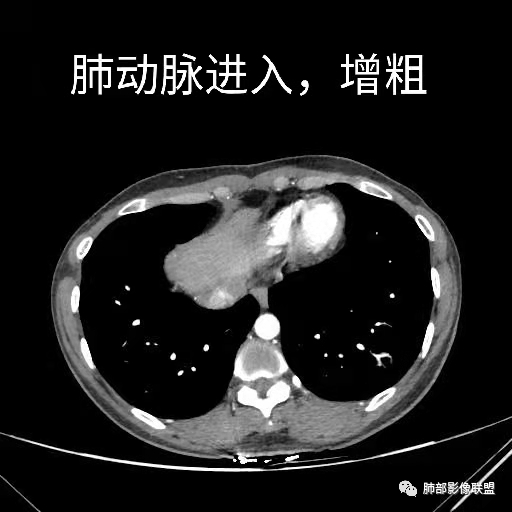

肺动脉供血

@张明辉临沂市人民医院 今天病例粗大肺动脉供血+空洞结节,和我上传病例比较像。

肺动脉为主征的话,PSP要考虑,还有贴边的意思

唐老师说的有道理,常规进入肿瘤的血管不会这么粗,PSP确实要考虑。